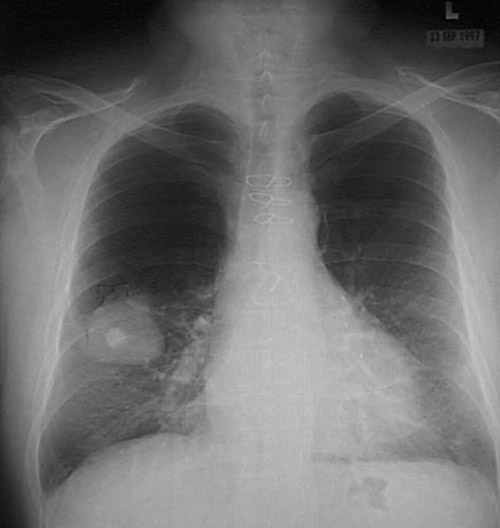

Click on the bronchogenic carcinoma in the chest radiograph above:

This chest radiograph demonstrates a large 5 cm diameter squamous cell carcinoma of the right lower lobe. The 1.5 cm bright opacity in the middle of the mass is a calcified granuloma that was seen on lateral view to be behind the neoplasm. Additional calcified granulomatous areas are medial to the mass. The sternal wire loops are from a previous coronary artery bypass procedure.